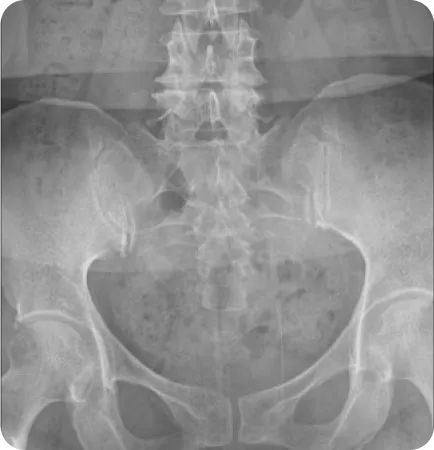

Pattern 01.

회전성 부정렬

골반이 앞뒤로 회전한 상태 (80~85%)

Ant.tilt (AS)

Post.tilt (PI)

Pattern 02.

골반 플레어 좁아진 골반과 벌어진 골반

골반 앞쪽이 벌어지거나 모인 상태 (40~50%)

Inflare (EX)

Outflare (IN)

Pattern 03.

업 슬립 골반 높이 차이

한 쪽 골반이 위로 올라간 상태 (15~20%)

Upsilp

Downslip